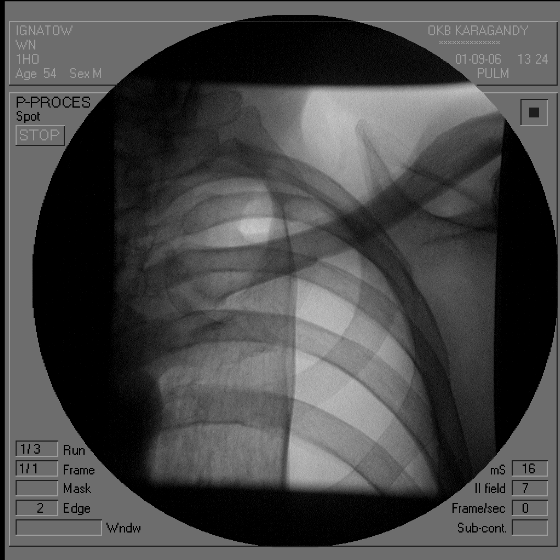

Каким патологическим субстратом обусловлен данный патологический процесс// +воздухом в плевральной полости// жидкостью в плевральной полости// инфильтрацией легочной ткани// полостью распада// спаечным процессом в плевральной полости

С чем связан механизм развития данного патологического процесса// со спонтанным разрывом легкого// с растеканием жидкости в плевральной полости// с инфильтрацией легочной ткани// с распадом легочной ткани// +со спаечным процессом в плевральной полости